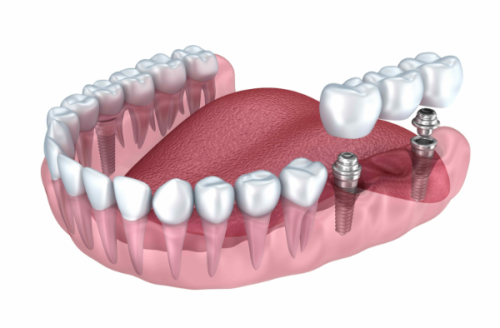

活动义齿一般多少钱一颗费用?2026年最新价格揭秘! 文章揭秘2026年活动义齿最新价格。通常镶活动假牙一颗1000 - 3000元,不同类型费用有别。如隐形义齿1000 - 1200元,便宜但寿命短、咀嚼差;钴铬合金等1500 - 2000元,强度好、使用久;纯钛基托2000 - 3000元,舒适美观。此外,地区、医院等级和医生水平也影响价格,选义齿要综合考量。 活动义齿 2026年03月04日 0 点赞 0 评论 7 浏览